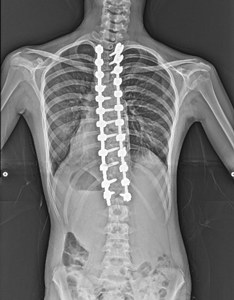

背中に固定するものが入っているので少し違和感がありますが、肩の高さがそろいました。

しかも身長が2cmも伸びました!

手術後のレントゲン画像